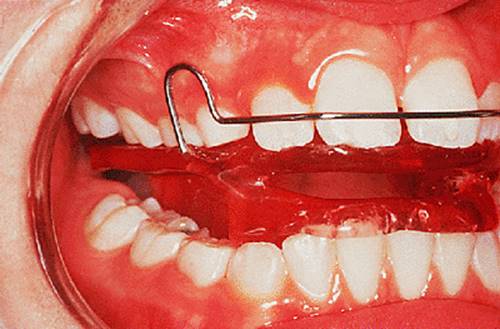

An alternative approach is to correct the upper incisor angulation by moving their crowns labially, which is often straightforward using a removable appliance. The resulting increased overjet and the deep overbite can then be corrected using a functional appliance. This method is particularly appropriate where the lower arch is well aligned. The retroclined upper incisors are often crowded, but this resolves as they are tilted labially into a larger arc. The malocclusion has then been changed from Class II division 2 to a Class II division 1 with aligned arches, which is ideal for treatment with a functional appliance (Fig. 18.3).

Fig. 18.3. (a) Class II division 2 malocclusion with well-aligned lower arch; (b) upper removable appliance to expand the arch and procline the upper incisors; (c) activator appliance in place; (d) some overcorrection was achieved.

image(a)

image(b)

image(c)

image(d)